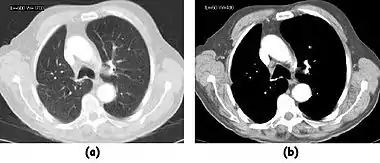

Fig. 7.15.2: Effect of window width and level on CT image display: (a) Level = 50; Width = 200. (b) Level = 50; Width = 400. The image in (a) is displayed with greater contrast and appears noisier than that in (b).

Fig. 7.15.3: Effect of window width and level: (a) Level = -600; Width = 1700. (b) Level = -60; Width = 400. Image (a) displays the lung tissue more clearly, while image (b) can be used to highlight any pulmonary lesions.

Examples of image display manipulation are shown in the two figures above. In Figure 7.15.2, the same image of a slice through a patient's liver is displayed using a relatively narrow window (high contrast) and also with a wide window. The image with the narrower window appears noisier, but this is merely a reflection of the fact that the gray scale is spread over a narrow range of CT-numbers.

Figure 7.15.3 illustrates the use of a relatively narrow window to highlight pathology in the lungs.